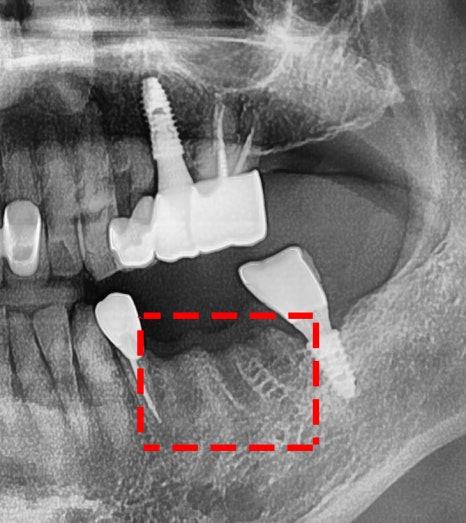

문제가 되는 아래 어금니를 살펴봅니다.

상태가 좋지 않네요.

내부는 더 깊게 썩어있는 상태였고,

그 옆에 있는 35번 작은 어금니 역시

마찬가지로 좋지 않은 상태였습니다.